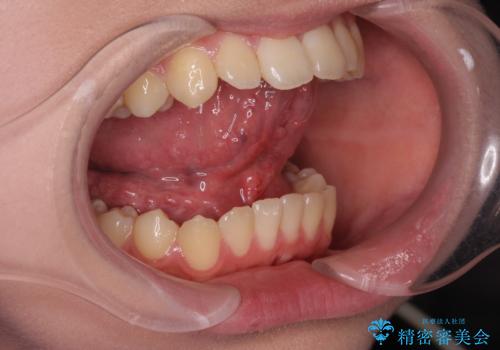

舌が短く話しづらい、滑舌を改善する小手術

- 「舌が短く話しづらい、サ行が発音しづらいので改善したい。」と希望され来院されました。

舌の動きを改善し、発音しやすくなるよう即日の小手術を計画します。